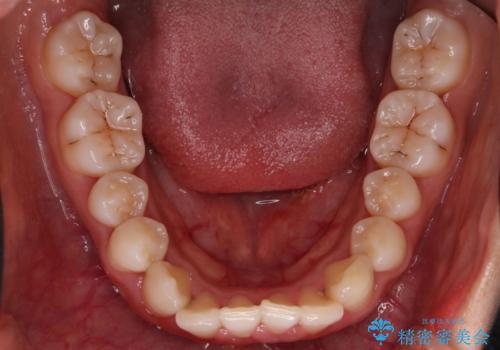

【インビザライン】八重歯が気になる

- 乳歯を抜歯してスペースを確保し八重歯の改善を行いました。

インビザラインをしっかり使用していただいたので、きれいな歯並びになりました。